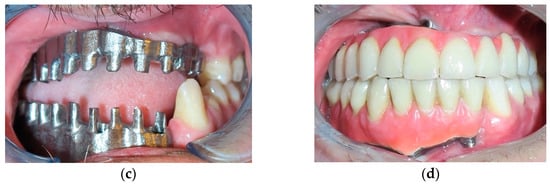

Figure 2.

(a) Radiography imaging before prosthetic rehabilitation; (b) Radiography imaging after implant surgery.

In the first case, a low-velocity ballistic trauma caused the loss of teeth 4.3, 4.2, 4.1, 3.1, and 3.2 and the loss of a large portion of gingiva and basal bone in mandibular area; an anterior alveolar resection of the mandible was performed, and the definitive reconstruction consisted of a surgical bone graft taken from the mandibular angle. Nine months after surgery bone reconstruction, the implant surgery was performed, and four implants, namely “Zimmer Trabecular Metal”, were inserted in anterior lower maxilla. In the same area, a fornix depth was performed. After four months, healing screws were inserted, and three months later, the patient finalized the treatment with five metal/ceramic crowns (primary metal structure and secondary ceramic structure) (Figure 1, Figure 2 and Figure 3).